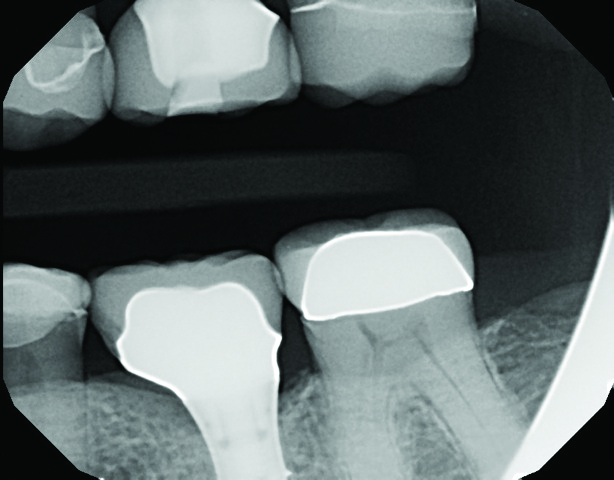

A 64-year-old woman presented with a chief complaint of food packing to the front of her implant. Clinical and radiographic examination revealed an existing Straumann Soft Tissue Level (RN) implant (Straumann, straumann.us) for tooth No. 19, restored with a prefabricated solid abutment and a PFM crown. The mesial marginal ridge of the PFM No. 19 was fractured, leaving an open proximal space between No. 19 and No. 20 (Figure 1).

Fig 1. The mesial marginal ridge of the PFM tooth No. 19 is fractured, leaving an open proximal space between teeth Nos. 19 and 20.

Figure 1